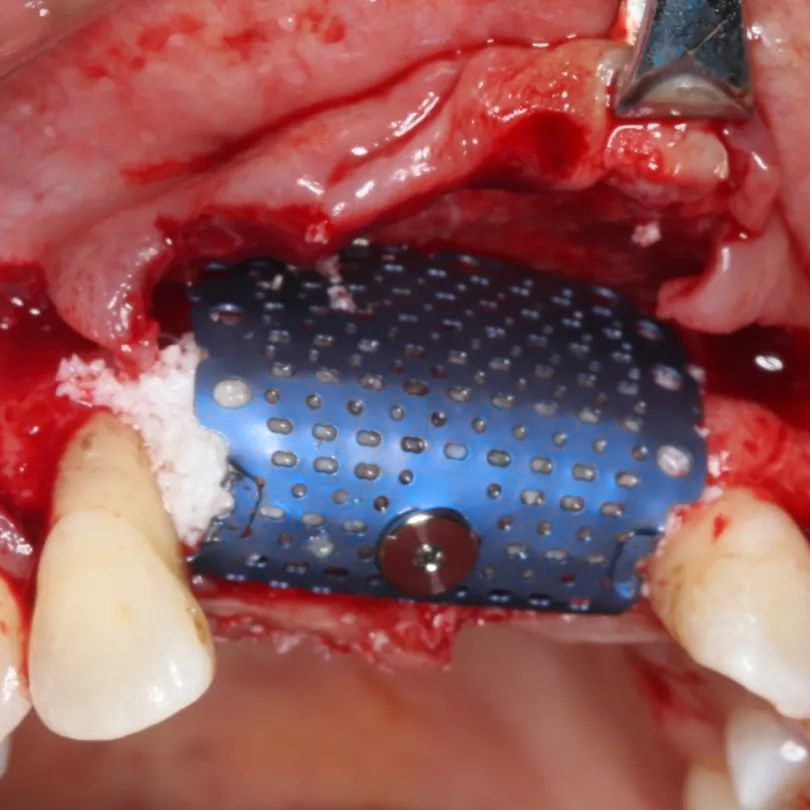

Our Titanium Mesh Membrane is designed to offer optimal support in guided bone regeneration (GBR) procedures, combining structural stability with excellent adaptability. The ultra-thin, anatomically contoured design allows for a comfortable fit and easy surgical handling, while maintaining strong support for the defect area. It can be easily trimmed and shaped to match various bone contours, making it a reliable and versatile choice in both simple and complex cases.

Enhanced fixation: Designed to be used with bone tacks for stable placement

Perforated (lightening) holes: Ensure good vascularization and promote blood supply to the regeneration site